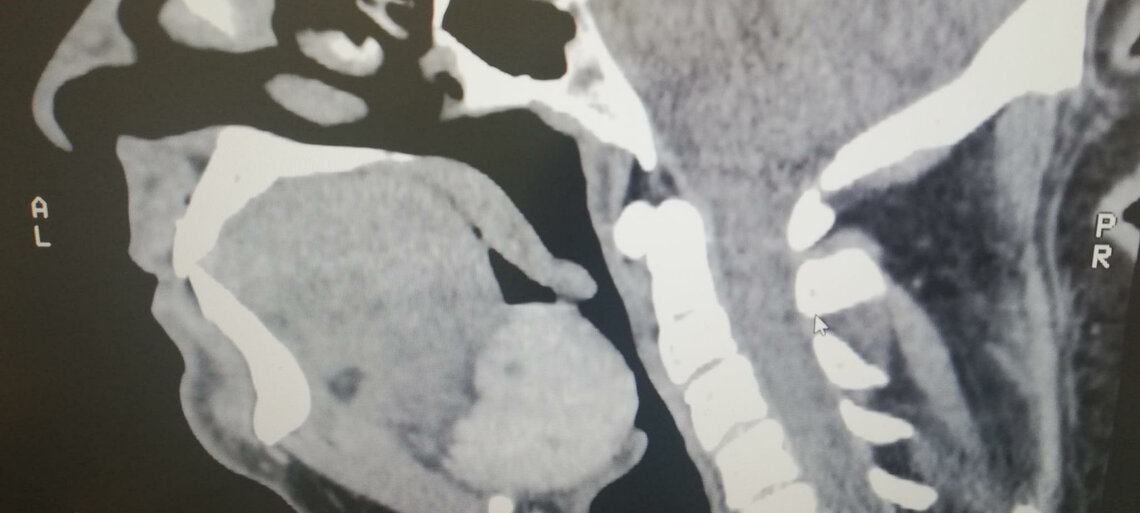

La tiroide linguale è una rara anomalia congenita in cui il tessuto tiroideo, invece di trovarsi nel collo come normalmente avviene, è localizzato alla base della lingua. Si tratta della forma più comune di tiroide ectopica e può essere scoperta casualmente oppure manifestarsi con sintomi legati alla respirazione, deglutizione o fonazione.

Durante lo sviluppo embrionale, la ghiandola tiroidea si forma alla base della lingua e discende progressivamente nel collo fino a posizionarsi davanti alla trachea. In alcuni casi, questo percorso non si completa e il tessuto tiroideo resta localizzato in sede linguale, originando la tiroide linguale, una variante di tiroide ectopica. In molti pazienti, questo tessuto rappresenta l’unica tiroide presente.

Diagnosi della tiroide linguale

La diagnosi richiede una combinazione di valutazioni cliniche e strumentali:

- Visita specialistica con ispezione della base della lingua;

- Ecografia del collo, per verificare l'assenza di tiroide in sede normale;

- Scintigrafia tiroidea con iodio-123 o tecnezio-99m: è l’esame più specifico;

- TAC o RMN per valutare l'estensione e la posizione del tessuto;

- Esami del sangue per valutare la funzione tiroidea (TSH, FT3, FT4).